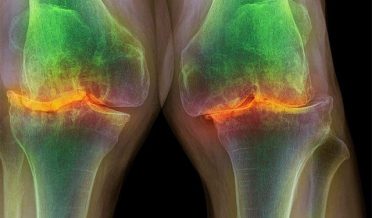

جوڑوں کے مرض میں درد کے علاج کیلئے جدید پیشرفت